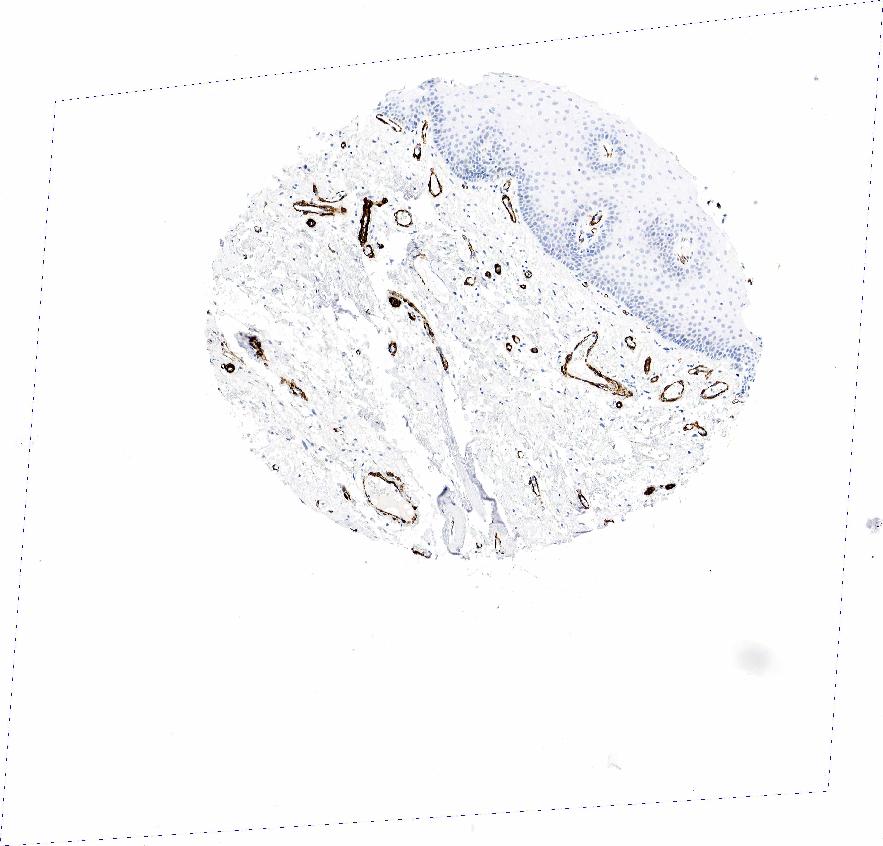

ORAL MUCOSA - Antibody stainingi

Antibody staining in the annotated cell types in the current human tissue is reported as not detected, low, medium, or high, based on conventional immunohistochemistry profiling in selected tissues. This score is based on the combination of the staining intensity and fraction of stained cells.

Each image is clickable and will lead to virtual microscopy that enables deeper exploration of all samples and also displays staining intensity scores, fraction scores and subcellular localization as well as patient and tissue information for each sample.

Antibody HPA041264Antibody HPA041271Antibody CAB000002Antibody CAB003761Antibody CAB013531

Squamous epithelial cells MediumNot detectedNot detectedNot detectedNot detected